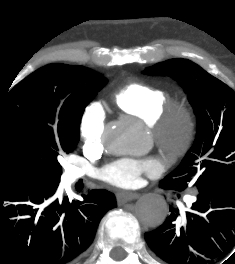

Компьютерная томография сердца является высокотехнологичным лучевым методом исследования, который позволяет оценить строение и особенности анатомии камер сердца, визуализировать состояние перикарда, коронарных артерий и восходящей части и дуги аорты.

В нашей клинике КТ сердца проводится на новейшем 128-срезовом мультиспиральном компьютерном томографе экспертного уровня TOSHIBA AQUILION CXL. Томограф послойно сканирует анатомическую область сердца, производя срезы толщиной от 0,5 мм. Методика сканирования сердца 128-срезовым КТ сканером производится с использованием перспективной синхронизации по электрокардиографии (ЭКГ).

Протокол сканирования предусматривает внутривенное болюсное контрастирование. Контрастное вещество на основе йода вводится пациенту внутривенно непосредственно во время исследования. Контраст равномерно распределяется по сосудистой системе, благодаря чему становится хорошо видна восходящая часть аорты с отходящими от нее венечными артериями и дуга аорты. По результатам обследования можно решить, нуждается пациент в проведении стентирования коронарных артерий или нет.